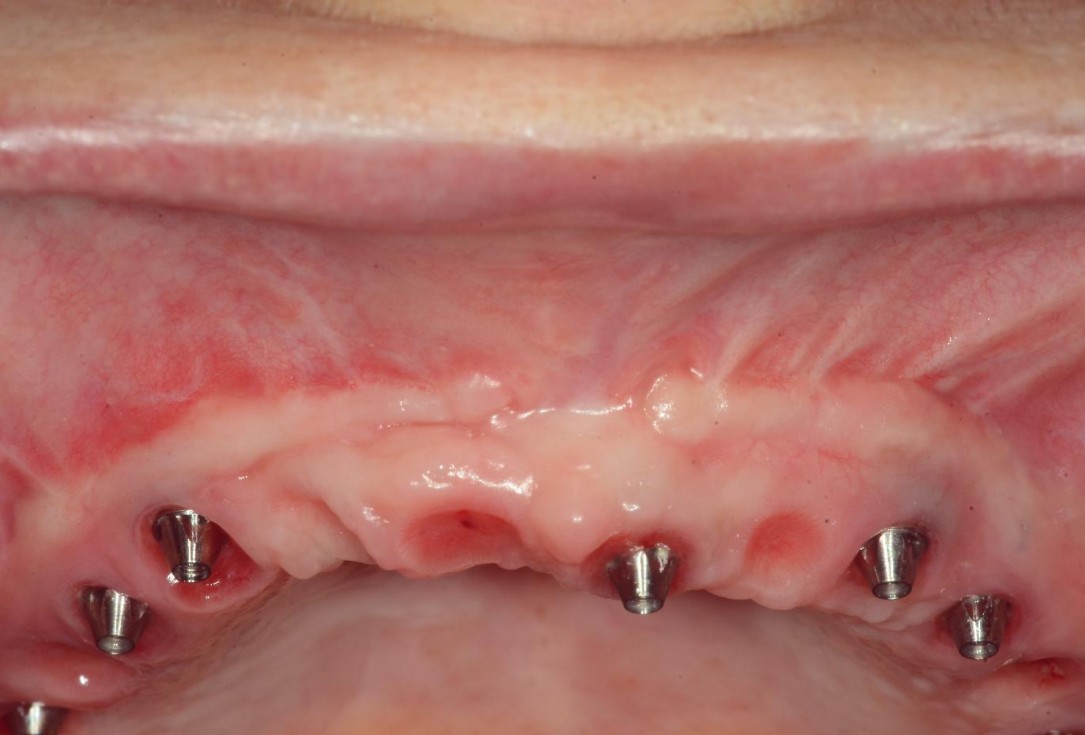

2/8 - Split-flap preparation with intact periosteal layer and apical fixation of the buccal flapmucoderm® for full arch reconstruction of insufficient vestibular depth and lack of keratinized tissues - Dr. B. Mólnar & Prof. P. Windisch